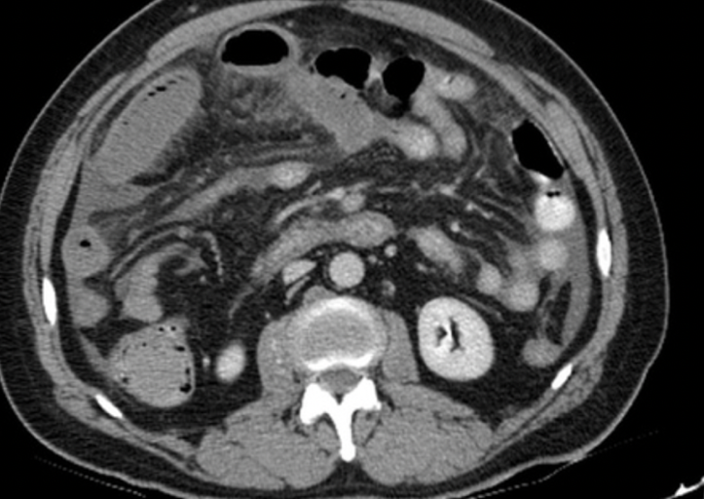

Caso clinico 2

Paziente con dolore addominale severo, lattati elevati. APR: Fattore V di Leiden.

Perché la parete intestinale appare ipodensa nonostante sia presente enhancement mucoso?

- Vasospasmo arterioso diffuso

- Necrosi mucosa selettiva

- Edema sottomucoso da congestione venosa

- Riduzione del flusso arterioso

- Presenza di aria intramurale

Risposta corretta: C

COMMENTO

Nell’infarto venoso:

- il problema è nel deflusso → ↑ pressione capillare

- stravaso di liquidi → edema sottomucoso

- mucosa può ancora captare inizialmente

Risultato:

- pattern “a bersaglio”

- centro ipodenso (edema)

- mucosa periferica con enhancement

Insight: arterioso ≠ venoso

- arterioso → parete sottile, ipoenhancement

- venoso → parete ispessita, edema marcato